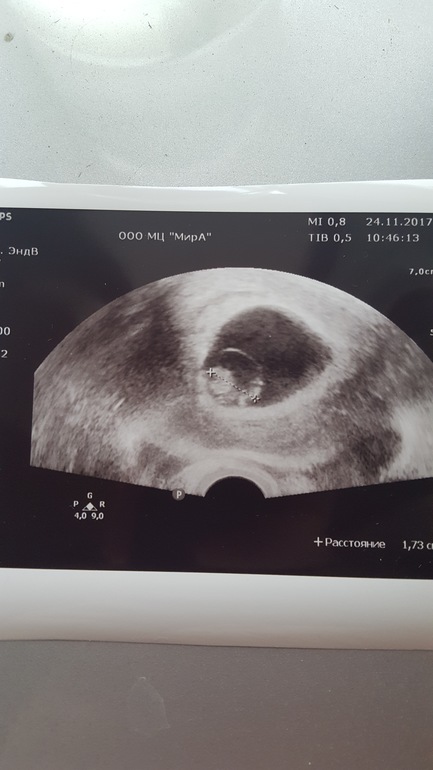

Узи 7+5. Мы растём!

Ктр 1.73 (ре сказала "ого", что я перевожу как "отлично" :).

Сб ясное, ритмичное. Звук почему-то не включали, а я забыла попросить. :(

Ракурс на фото какой-то странный, кроме головы опознать ничего не могу :)

Сверили наши расчёты - мне приложение показывало 8+2, по её расчётам 7+5.